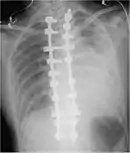

CT scan of the chest showing a hemothorax caused by warfarin use